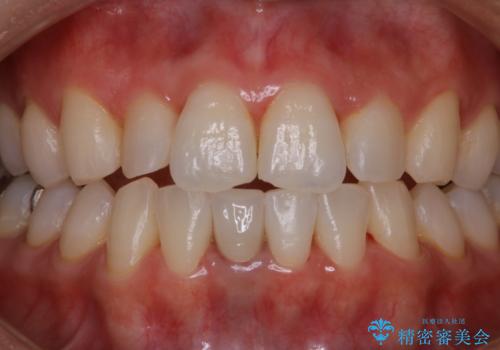

- 夜間の歯ぎしり・食いしばり予防のナイトガードを作成希望とのことで来院されました。しばらくクリーニングも受けていないとのことでPMTC30分コースを行いました。

プラークや歯石により、歯肉が炎症している場合、歯と歯肉の境目が鮮明に型取り出来ないなどがあります。そのため、マウスピースの作成前などには、PMTCで歯の表面の汚れを落とすことで、仕上がりのマウスピースがより精密なものとなります。